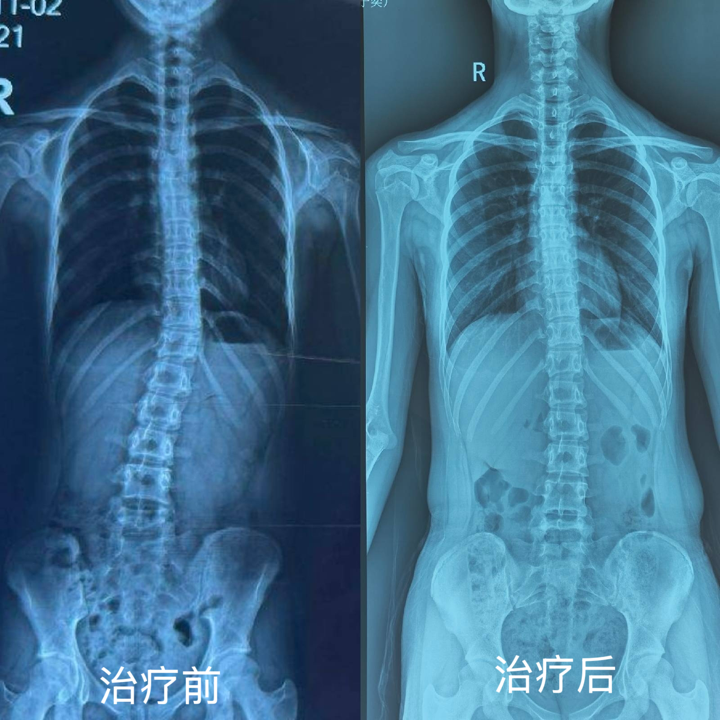

“孩子脊柱侧弯终于矫正了,现在身姿挺拔,再也不用自卑了!” 近日,市民王女士带着 14岁的女儿小宇(化名)在海顾外科踏踏虎儿童足脊健康管理中心复查时,对治疗效果赞不绝口。由海顾医疗团队首创居于国内领先地位的 “足脊一体化生物力学矫正体系”已成为国内青少年脊柱侧弯治疗的首选。

针对小宇的病情,张鑫主任及团队康复主管王娜为其定制了个性化足脊一体化矫正方案。通过 3D 足底压力检测、步态分析、脊柱全长片等多维度评估,精准锁定力学失衡关键点;由足踝医生与矫形支具师联合设计生物力学足垫及侧弯矫形器,精准支撑足弓、调整足底受力并控制侧弯进展;康复团队一对一指导肌筋膜链训练,强化核心肌群,同步调整脊柱力线;同时建立动态生长档案,每 3 个月根据发育情况优化方案,确保覆盖生长黄金窗口期。

“骨科医生必须具备系统思维,该体系的核心是‘从足到脊,全域联动’。” 张鑫主任介绍,作为国内唯一由专业足踝外科医生领衔的 “三师” 团队(医师 + 康复师 + 矫形支具师),他们创造性地将足踝矫正与脊柱干预相结合,通过矫正足弓根源性问题,阻断力学异常传导,实现脊柱侧弯的同步矫正。临床数据显示,该体系可使患儿足弓形态显著改善,脊柱侧弯度数有效控制,治疗有效率达 95% 以上。